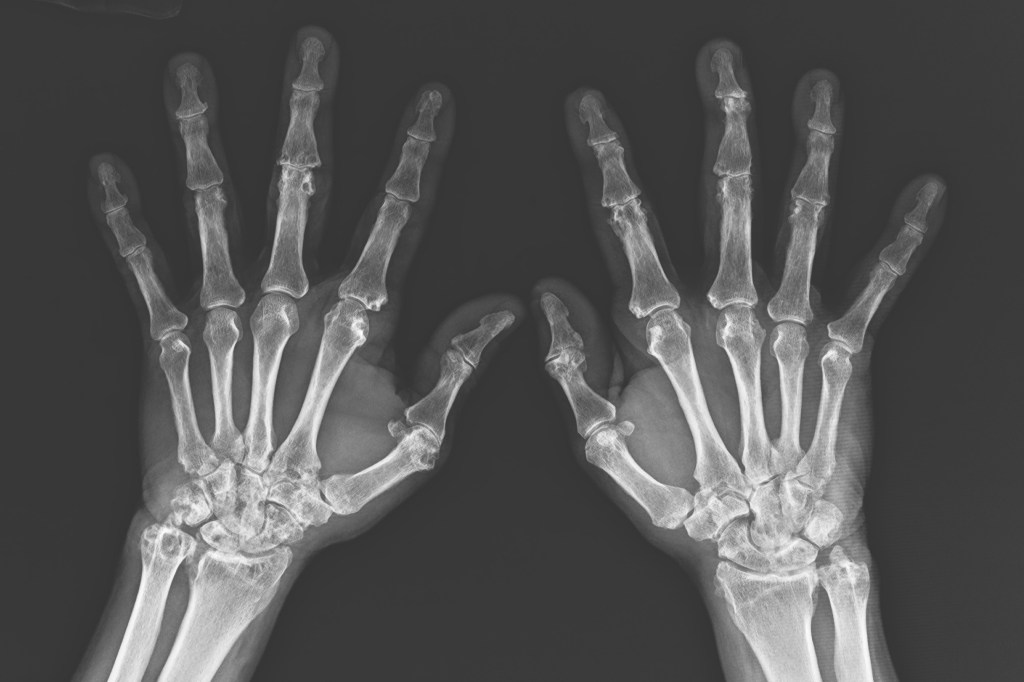

在手指實圖中看不出來有明顯變形的問題,可是在X光上已經出現明顯的關節侵蝕。

以左手為例,在左手的手腕骨有多處的痛風石侵蝕,造成骨頭多了好幾個洞,像是起司一樣。在左手大拇指、食指、中指的關節(圈選處)也都留下了侵蝕的痕跡。至於右手,痛風石也留下多處的關節侵蝕,右手腕的關節面也變窄了。

P先生的雙手關節已留下多處侵蝕的證據。

圈選出可看出痛風石曾經侵蝕骨關節的痕跡。